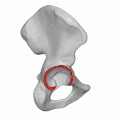

Суставные полулунные поверхности вертлужных впадин тазовых костей участвующие в образовании тазобедренных суставов (левого и правого) отмечены красным